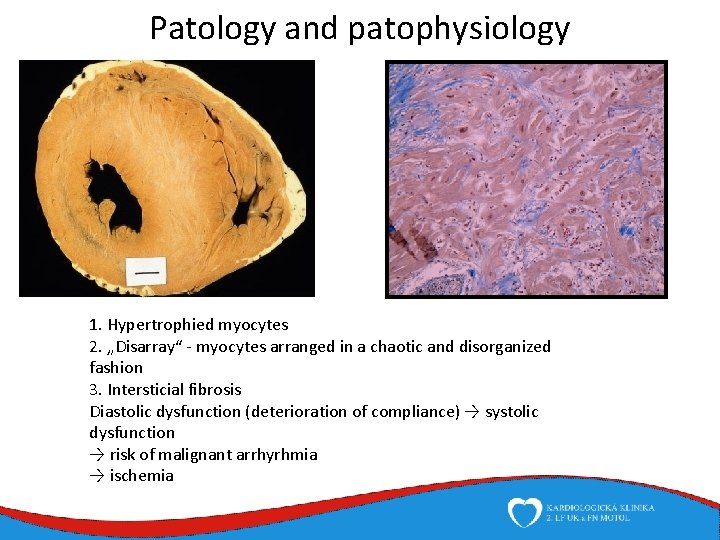

Patology and patophysiology 1. Hypertrophied myocytes 2. „Disarray“ - myocytes arranged in a chaotic and disorganized fashion 3. Intersticial fibrosis Diastolic dysfunction (deterioration of compliance) → systolic dysfunction → risk of malignant arrhyrhmia → ischemia